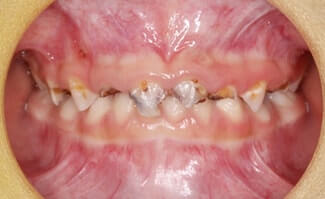

齲蝕(虫歯)